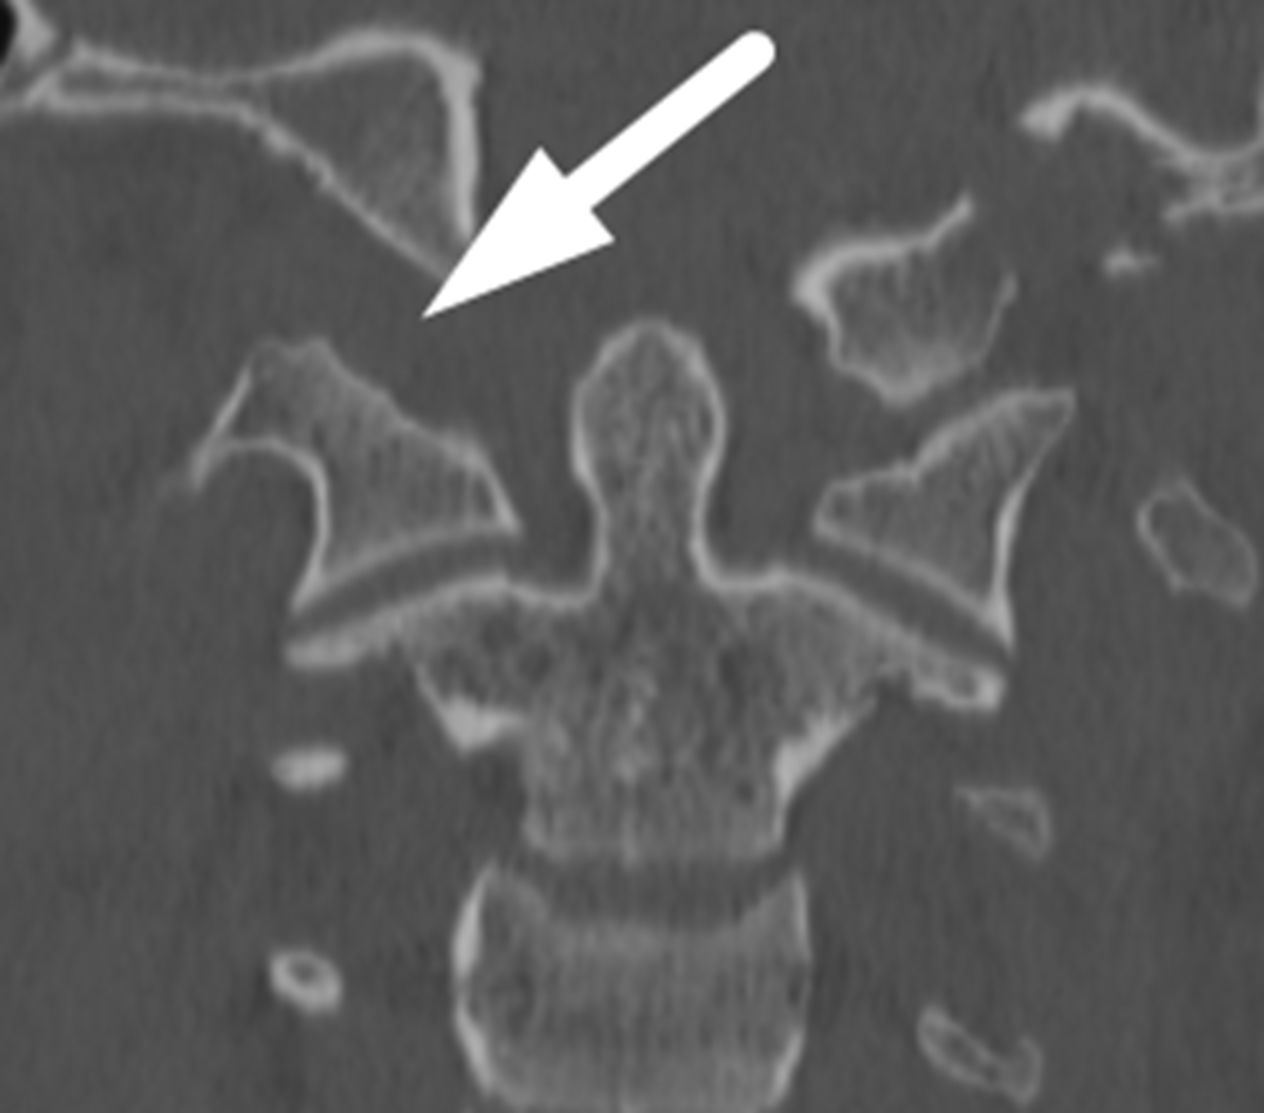

White arrow: widening of the right atlanto-occipital articulation.